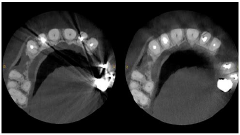

Endodoncia

Las imágenes de alta resolución (hasta 75 μm) se adaptan perfectamente a las indicaciones de endodoncia y ahora pueden capturarse en modos de maxilar individual y doble y campo de visión focalizado